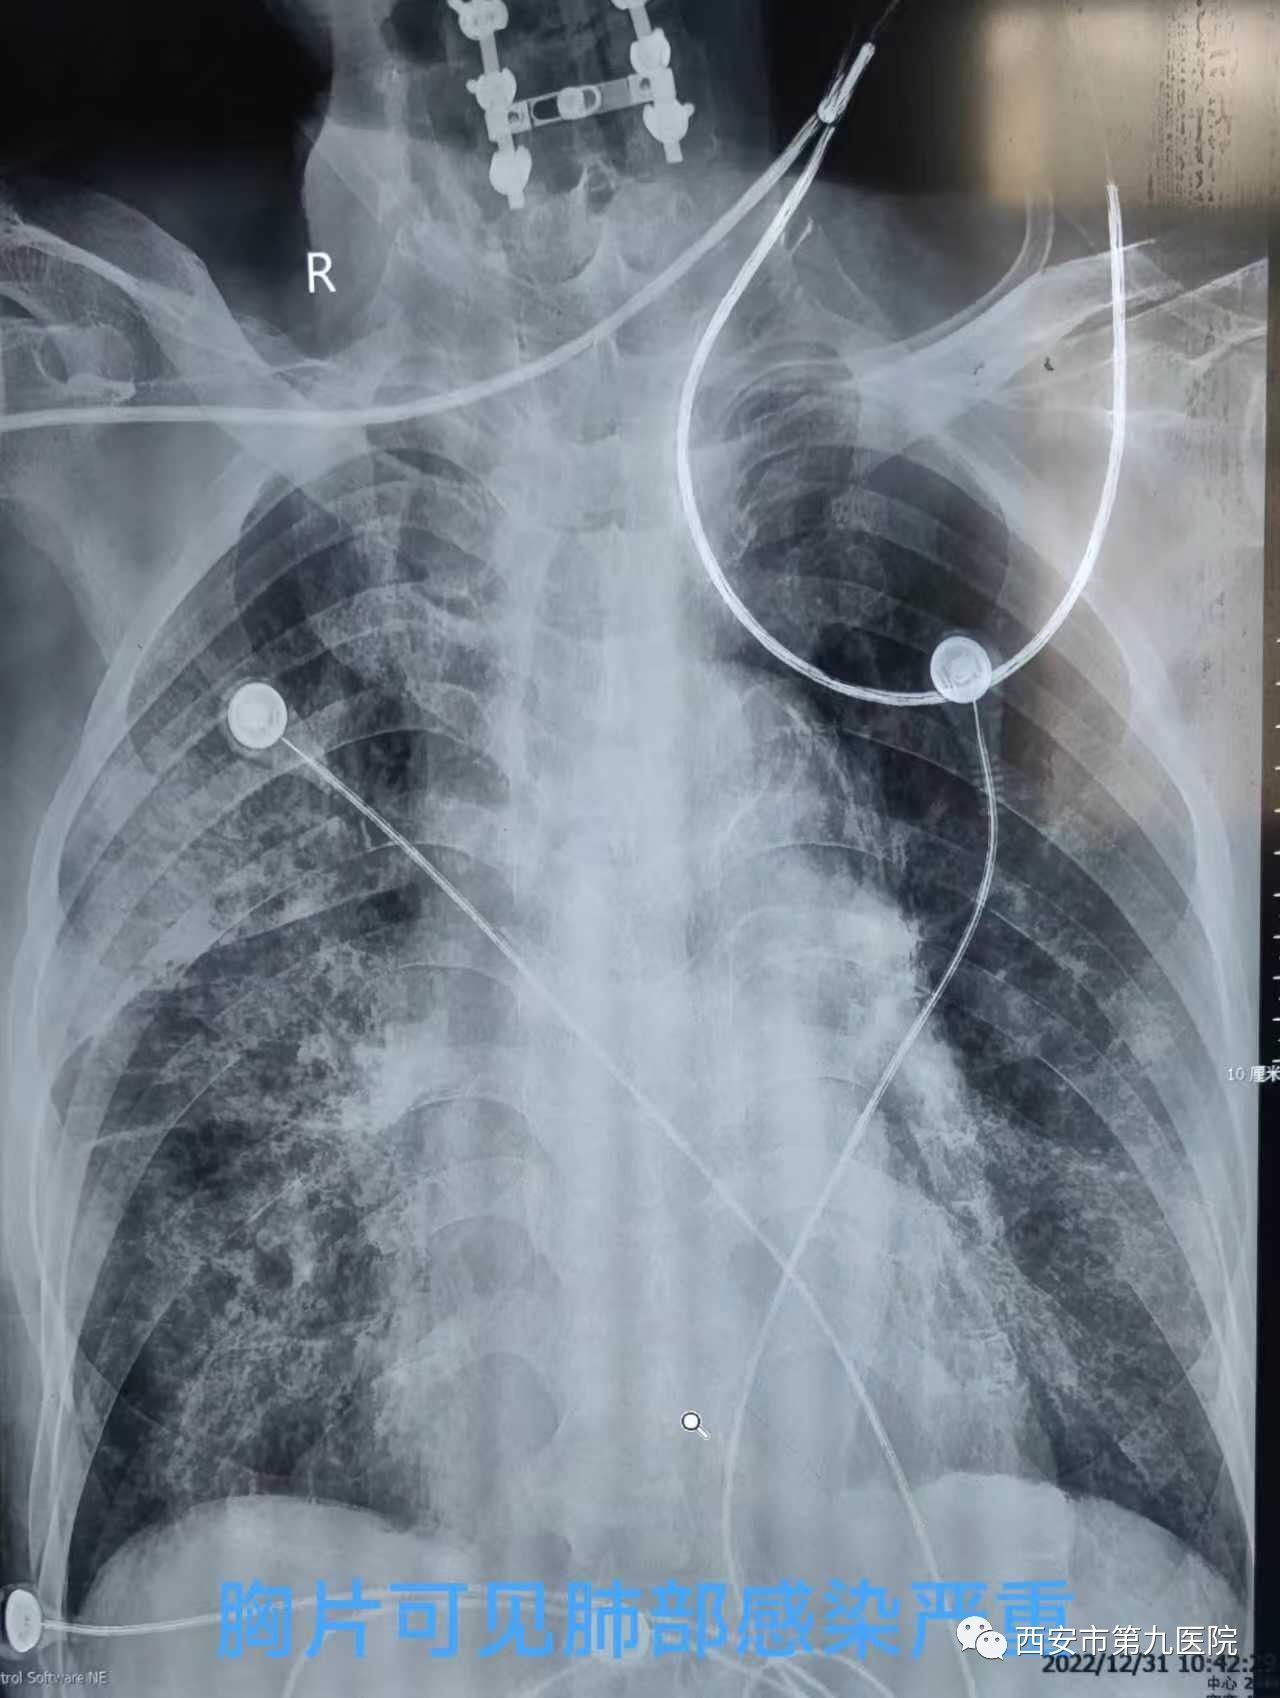

正当患者家属与医生同时松了一口气的时候,一个更加严峻的挑战摆在了大家面前,老人的核酸结果是阳性的,而且CT上可以看见已经出现少量的斑片状“白影”,由于术后老人左侧肢体偏瘫,需要长期卧床,而且意识情况依然不好,无法自主咳嗽咳痰,这势必会导致肺部炎症进展,果然,术后第5天,老人的肺部炎症加重了,并且合并了细菌感染,血氧饱和度只能维持90,同时心脏功能也濒临衰竭。